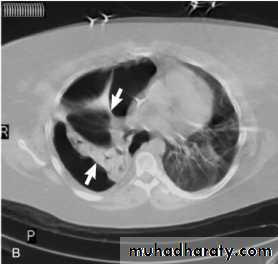

On a posteroanterior chest x-ray (A), the left hemithorax is very dark or lucent because the left lung has collapsed completely (white arrows).The tension pneumothorax can be identified because the mediastinal contents, including the heart, are shifted toward the right, and the left hemidiaphragm is flattened and depressed. A computed tomography scan done on a different patient with a tension pneumothorax (B) shows a completely collapsed right lung (arrows) and shift of the mediastinal contents to the left.

Tension Pneumothorax. Portable chest film in a 43-year-old woman with ARDS shows a large right pneumothorax with mediastinal shift and ipsilateral diaphragmatic depression, suggesting tension.

Air was evacuated under pressure during emergent placement of a right chest tube.